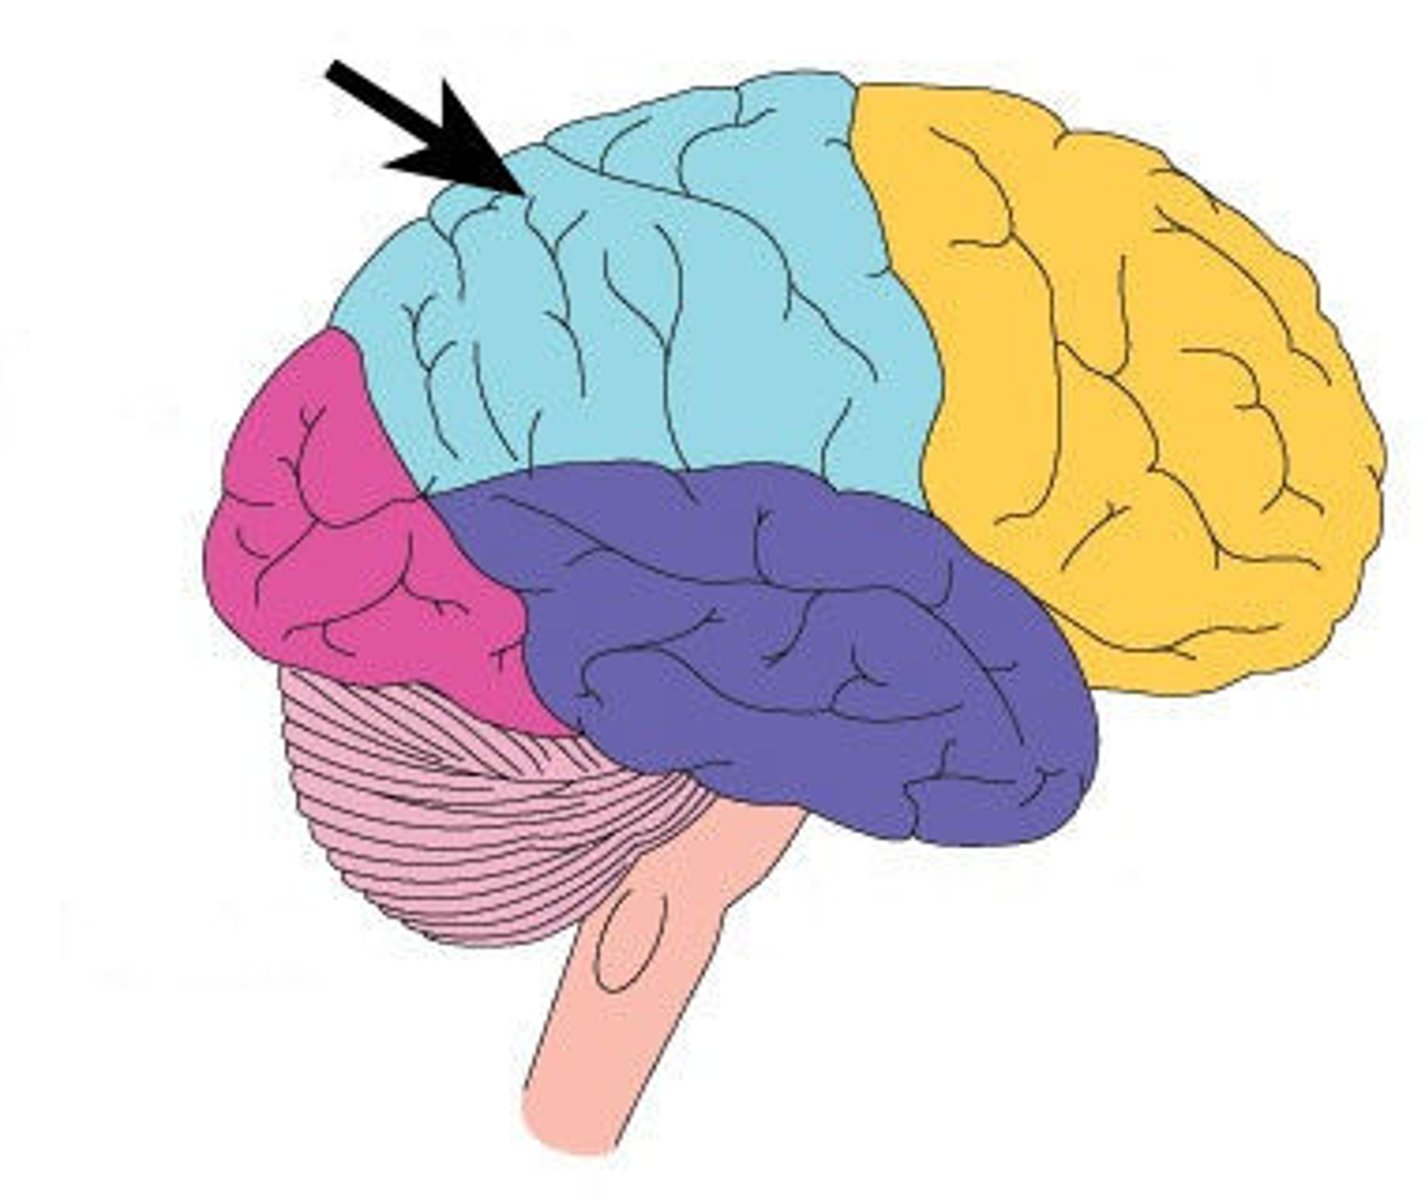

parietal lobe

A region of the cerebral cortex whose functions include processing information about touch, contains primary somatosensory cortex

postcentral gyrus

primary somatosensory cortex

central sulcus

between postcentral and precentral gyri

frontal lobe

associated with social cues, personality, planning, movement, emotions, and problem solving - contains primary motor cortex

precentral gyrus

primary motor cortex